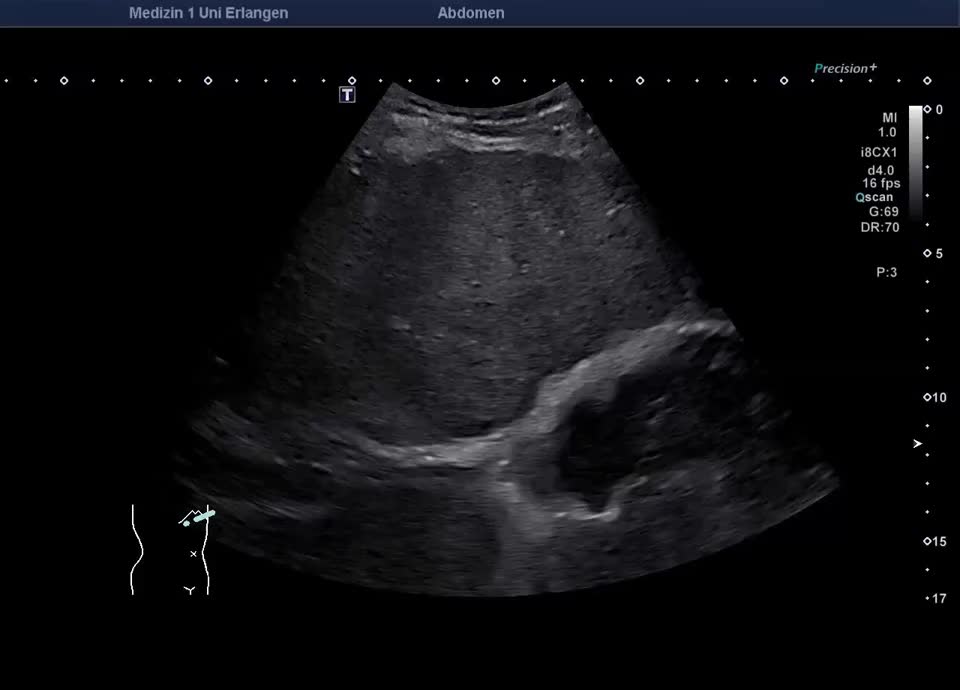

Cirrhotic changes

Dekompensierte Leberzirrhose mit Organschrumpfung und unregelmäßiger Leberoberfläche, Gallenblasenwand im Rahmen der portalen Hypertension verdickt (hochfrequenter Linearschallkopf)